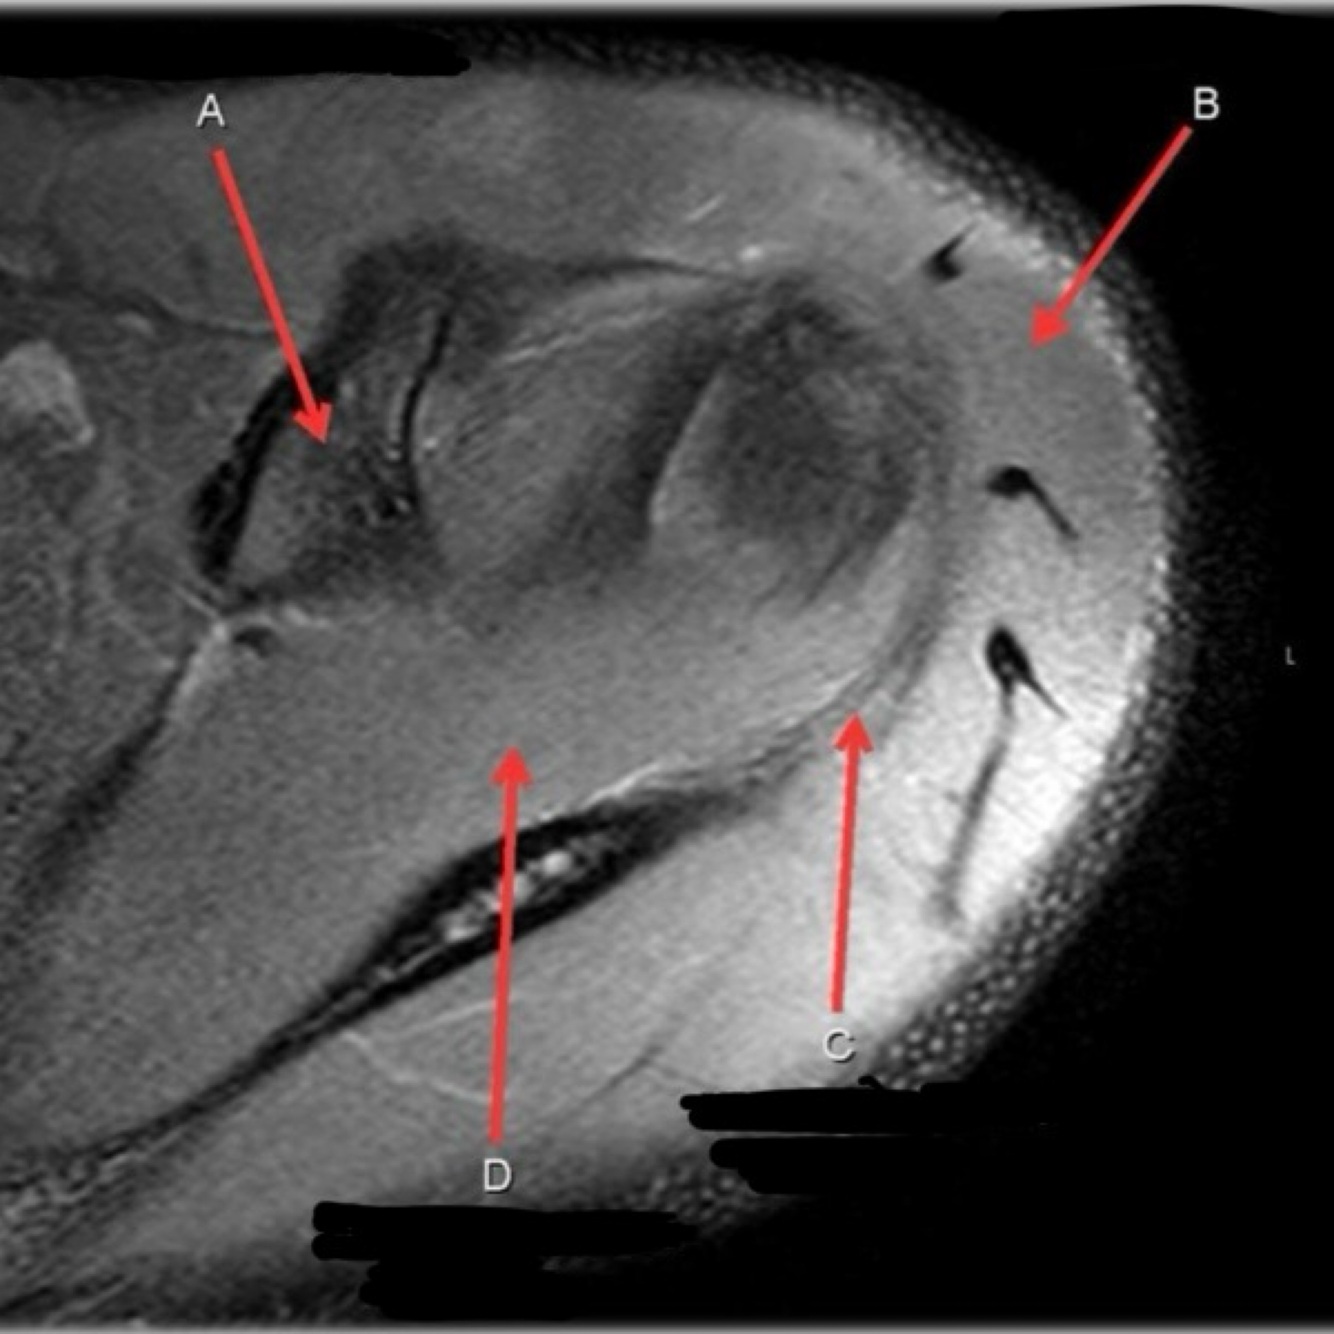

Q

What is letter A?

ANTERIOR LABRUM

12

What is letter B?

A

BICEPS TENDON (LONG HEAD)

How well did you know this?

1

Not at all

2

3

4

5

Perfectly

13

What is letter C?

HEAD OF HUMERUS

14

What is letter D?

POSTERIOR LABRUM